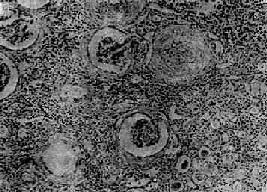

慢性肾盂肾炎

图12-25 慢性肾盂肾炎

有些肾小球毛细血管丛相对正常,肾球囊壁增厚,纤维化,部分肾小管萎缩消失,部分肾小管扩张,腔内有胶样管型;间质纤维组织增生,有大量淋巴细胞等炎细胞浸润